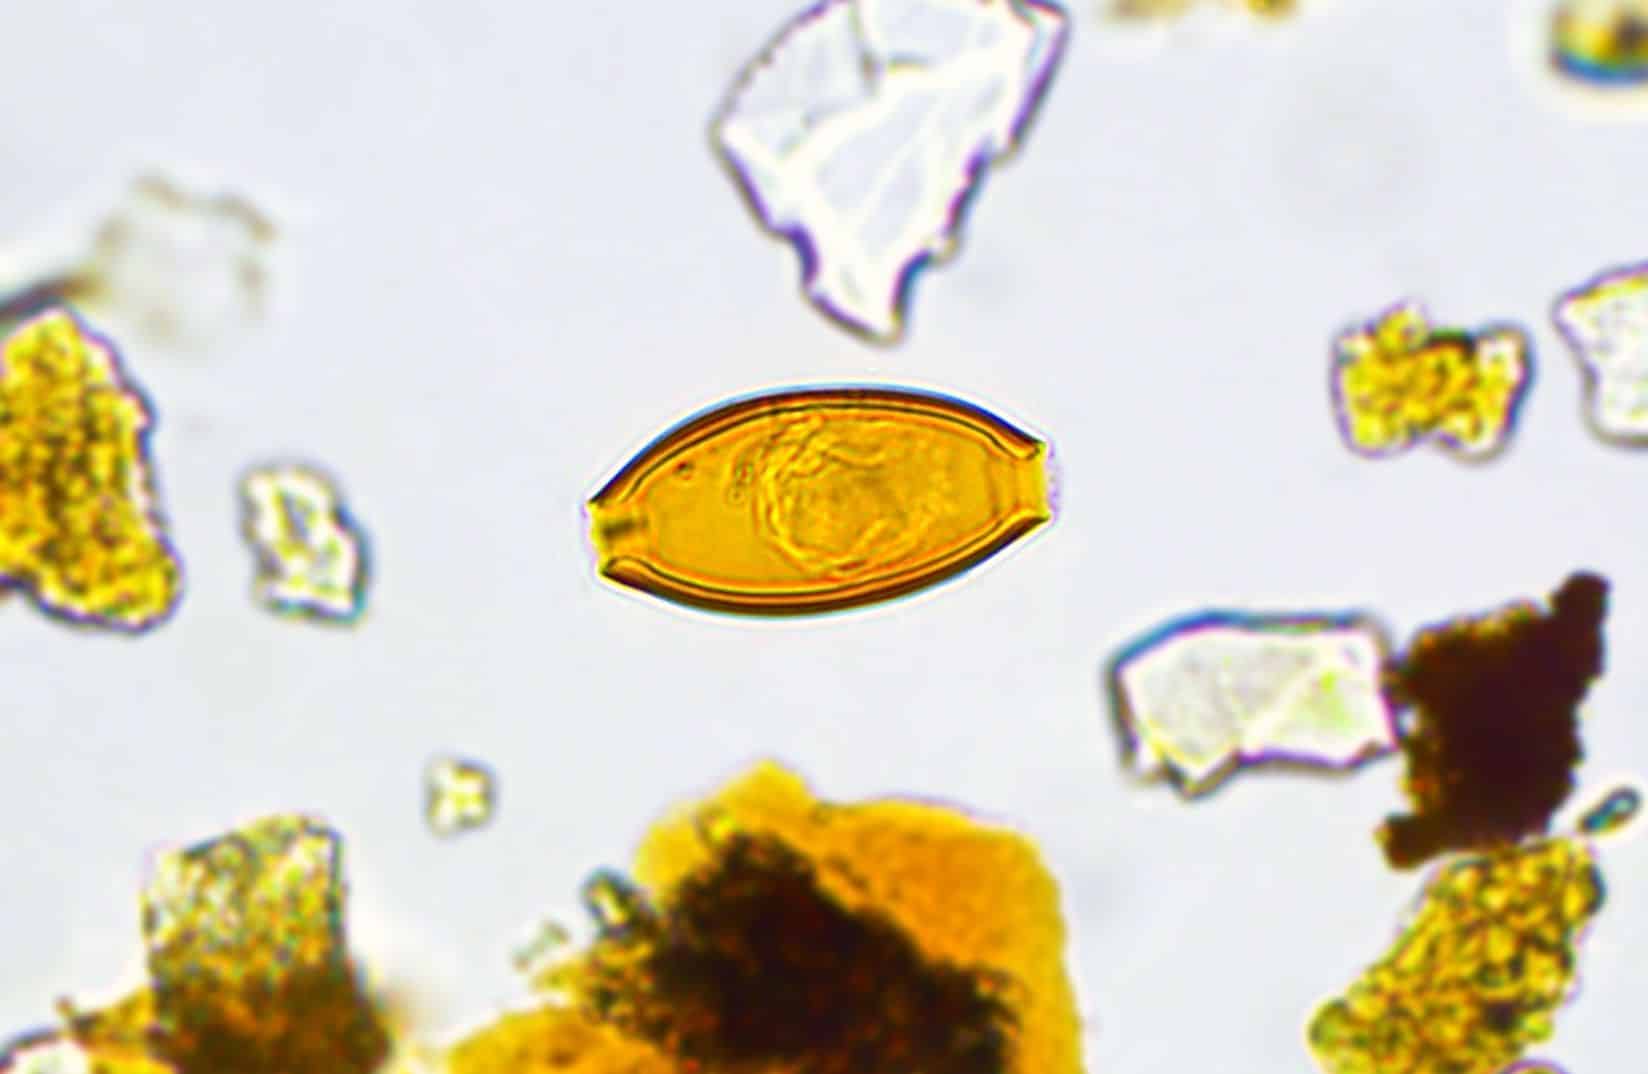

Présentation de l’image d’Aida Romera Barbera « Diagnostiquer le passé »

« Ce minuscule œuf de Trichuris trichiura est vieux de plus de 150 ans. Il a été retrouvé dans l’ancienne latrine d’une maison bourgeoise du début du 19e siècle, au cœur du Vieux-Limoilou à Québec. Bien que mort, son embryon est toujours visible en son centre. Sa découverte, une aubaine pour les archéoparasitologues, confirme qu’à cette époque, alors que les systèmes d’égouts n’existaient pas, plusieurs de nos ancêtres étaient aux prises avec la trichocéphalose, une maladie parasitaire intestinale occasionnée par T. trichiura. On estime aujourd’hui qu’il y a entre 450 millions et 1 milliard de cas actifs, et ce, surtout dans les pays chauds, humides et pauvres en infrastructures. (Taille de l’œuf : 43 µm | Grossissement : 400x | Microscopie optique) »